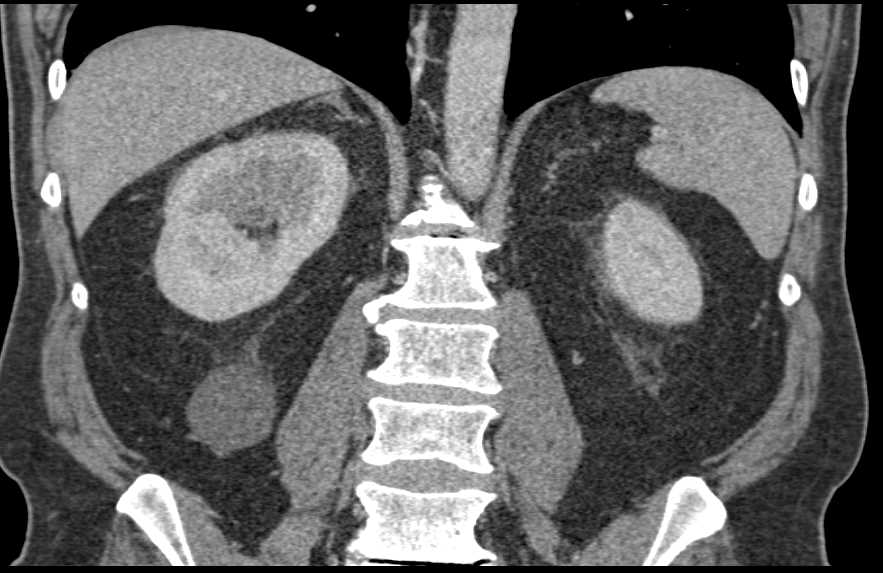

Acute Pyelonephritis Right Kidney